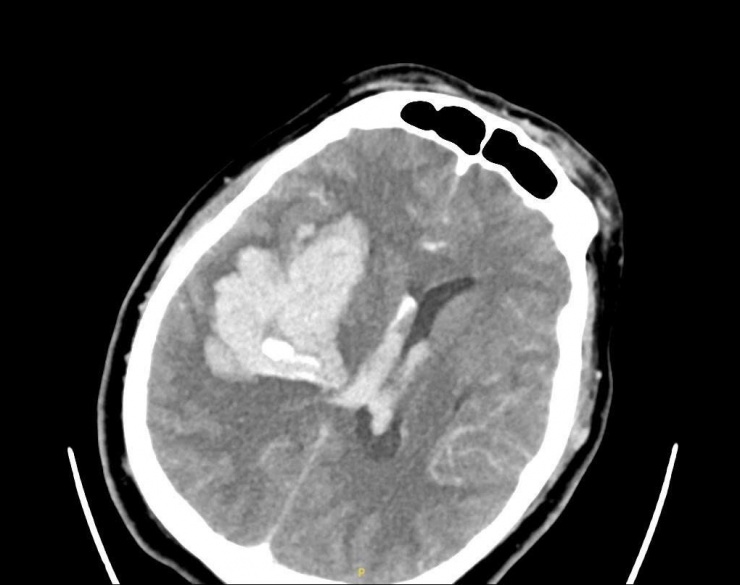

Hình ảnh phim chụp bệnh nhân bị xuất huyết não lượng lớn bán cầu phải. Ảnh: BVCC.

Kết quả CT não cho thấy ông V. bị xuất huyết não diện rộng. Bệnh nhân được đặt nội khí quản để bảo vệ đường thở và chuyển mổ cấp cứu ngay lập tức. Trong quá trình đặt ống nội khí quản, bác sĩ hút ra rất nhiều nước cốt chanh và cả cặn thuốc đọng trong họng. Nguyên nhân do người nhà cho bệnh nhân uống chanh, thuốc và chất lỏng tràn vào đường thở, làm người bệnh nguy kịch nhanh hơn. Sau một ngày cấp cứu, hiện bệnh nhân vẫn phải nằm hồi sức tích cực.